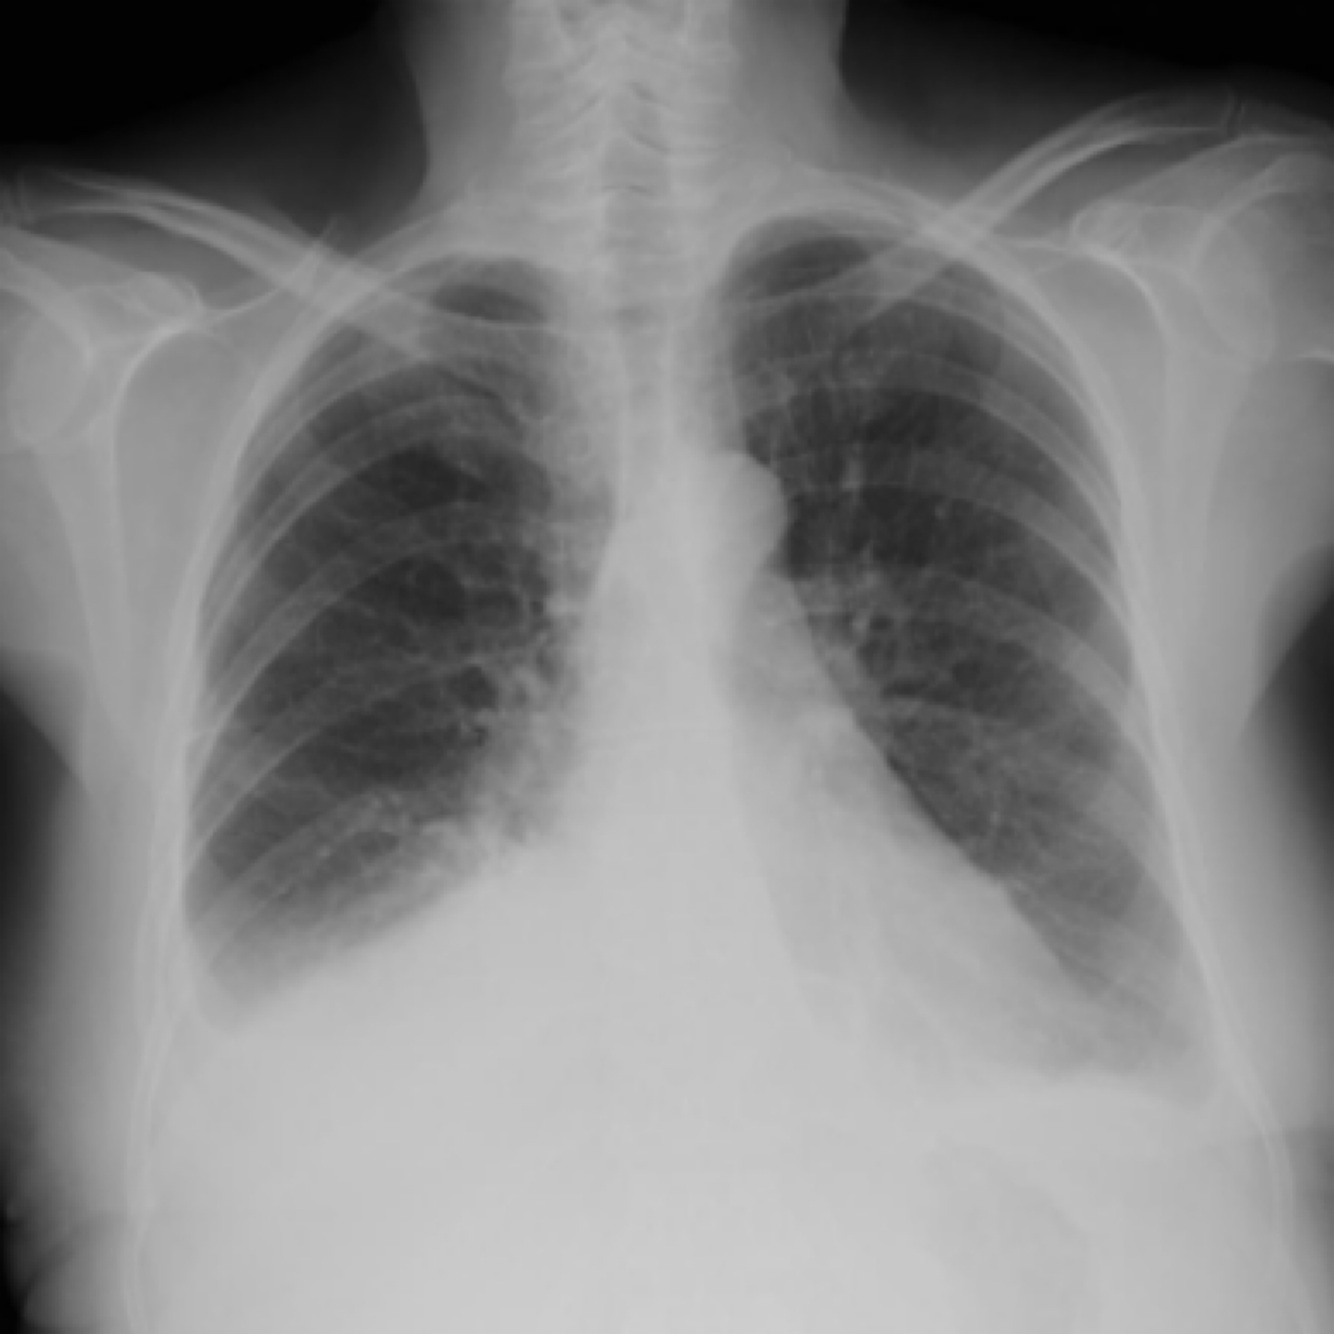

diffuse interstitial pneumonia